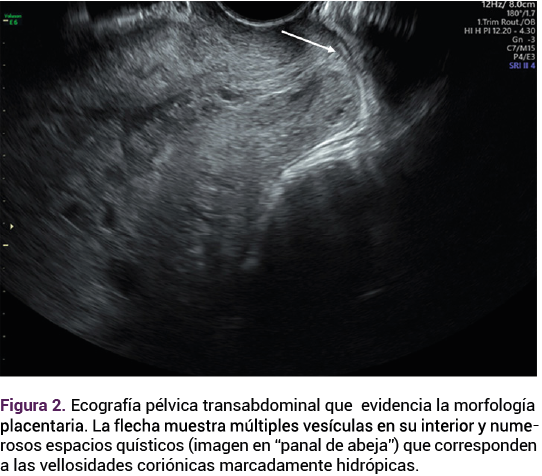

El ultrasonido pélvico transvaginal evidenció la existencia de un feto vivo de 12.6 semanas, por longitud cráneo-caudal (Figura 1), con discordancia de cavidades cardiacas ventriculares, comunicación intraventricular, ductus venoso patológico con onda invertida, translucencia nucal de 1.5 mm; placenta oclusiva total, con múltiples quistes en todo su espesor de 26 mm y vesículas a nivel placentario (imagen en “panal de abeja”) que corresponden a las vellosidades coriónicas marcadamente hidrópicas. Figura 2

<strong>Figura 2</strong>

Figura 2.